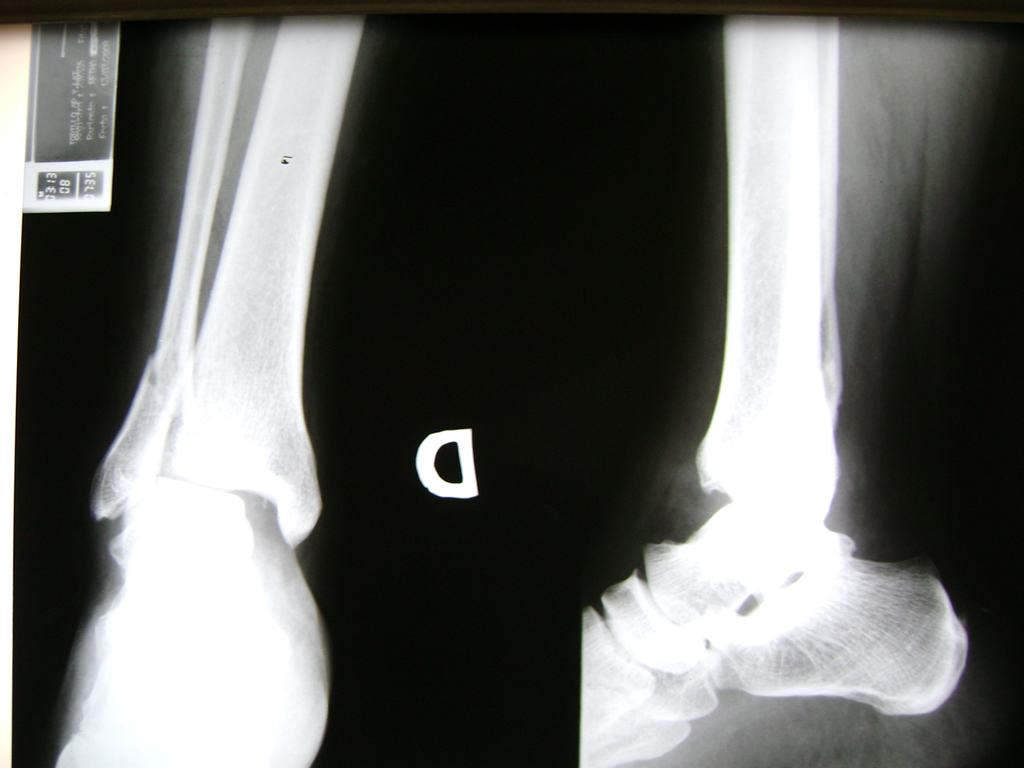

Una fractura de tobillo es la rotura de uno o más de los huesos del tobillo. Estas fracturas pueden ser:

- Parciales (el hueso está sólo parcialmente fisurado, no del todo).

- Completas (el hueso está perforado y está en 2 partes).

- Producirse en uno o ambos lados del tobillo.

Algunas fracturas de tobillo pueden requerir cirugía si:

- Los extremos de los huesos están desalineados entre sí (desplazados).

- La fractura se extiende hasta la articulación del tobillo (fractura intra-articular).